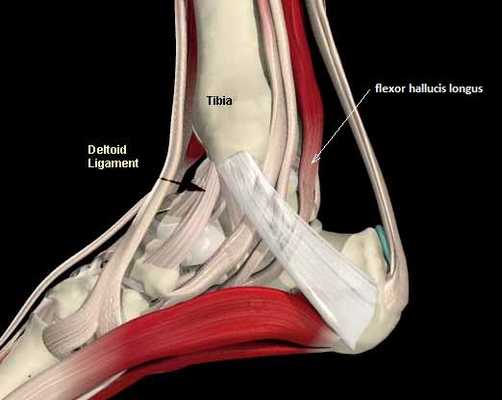

Введение.

Повреждения сухожилия сгибателя большого пальца стопы распространённый вид травмы в таких группах риска как танцоры (прежде всего балета), гимнасты и скалолазы. Эти группы людей объединяет существенная перегрузка сгибателя большого пальца стопы при выполнении толчков и зацепов, стояния на пуантах. Вторым названием данной патологии является «тендинит танцора». В остальной популяции данные повреждения встречаются крайне редко. Так как сухожилие длинного сгибателя большого пальца проходит в фиброзно-костном канале позади внутренней лодыжки и голеностопного сустава, оно оказывается как бы перекинутым через задний отросток таранной кости, как верёвка перекинутая через блок.

Прежде всего, это боль по задне-внутренней поверхности голеностопного сустава. Возможно «защёлкивание» большого пальца при его сгибании. Хруст, крепитация по задне-внутренней поверхности голеностопного сустава при активных движениях. При физикальном осмотре определяется боль при сгибании большого пальца через сопротивление, при форсированном подошвенном сгибании в голеностопном суставе, при этом боль отсутствует в области первого плюсне-фалангового сустава. Для диагностики повреждения сухожилия длинного сгибателя большого пальца стопы целесообразно выполнение МРТ, при этом обнаруживается скопление жидкости вокруг сухожилия на уровне голеностопного сустава, изменение сигнала от самого сухожилия.

Техника операции при тендините длинного сгибателя большого пальца стопы.

Для хорошей визуализации рекомендуется использование жгута. Выполняется полукруглый разрез параллельно заднему краю внутренней лодыжки. Необходимо аккуратно выделить сосудисто-нервный пучок и взять его на держалку. Доступ к сухожильному каналу можно осуществить как спереди так и сзади по отношению к пучку. На этом этапе возможно выделение сухожилия, после его тщательного осмотра и пальпации, удаляются все узлы, спайки. При обнаружении треугольной кости необходимо её удалить.